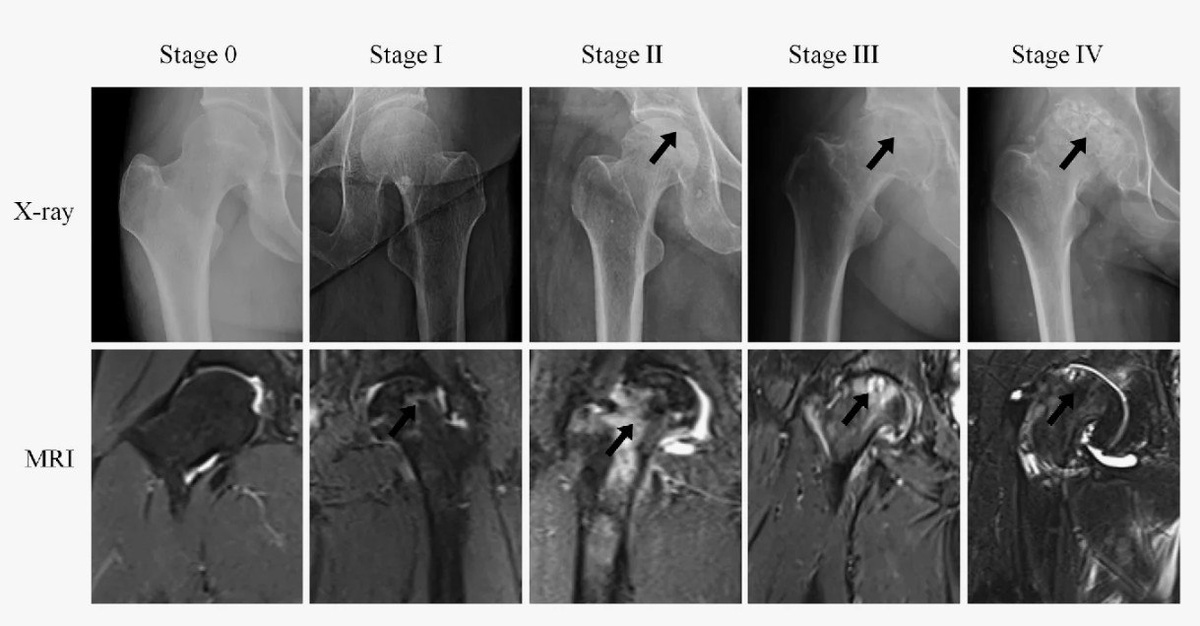

Оценка по шкалам VAS и Harris Hip Score, а также по данным МРТ.

• Часто наблюдается уменьшение очага некроза по МРТ.

• На ранних стадиях (ARCO I–II) УВТ эффективнее декомпрессии и костной пластики.